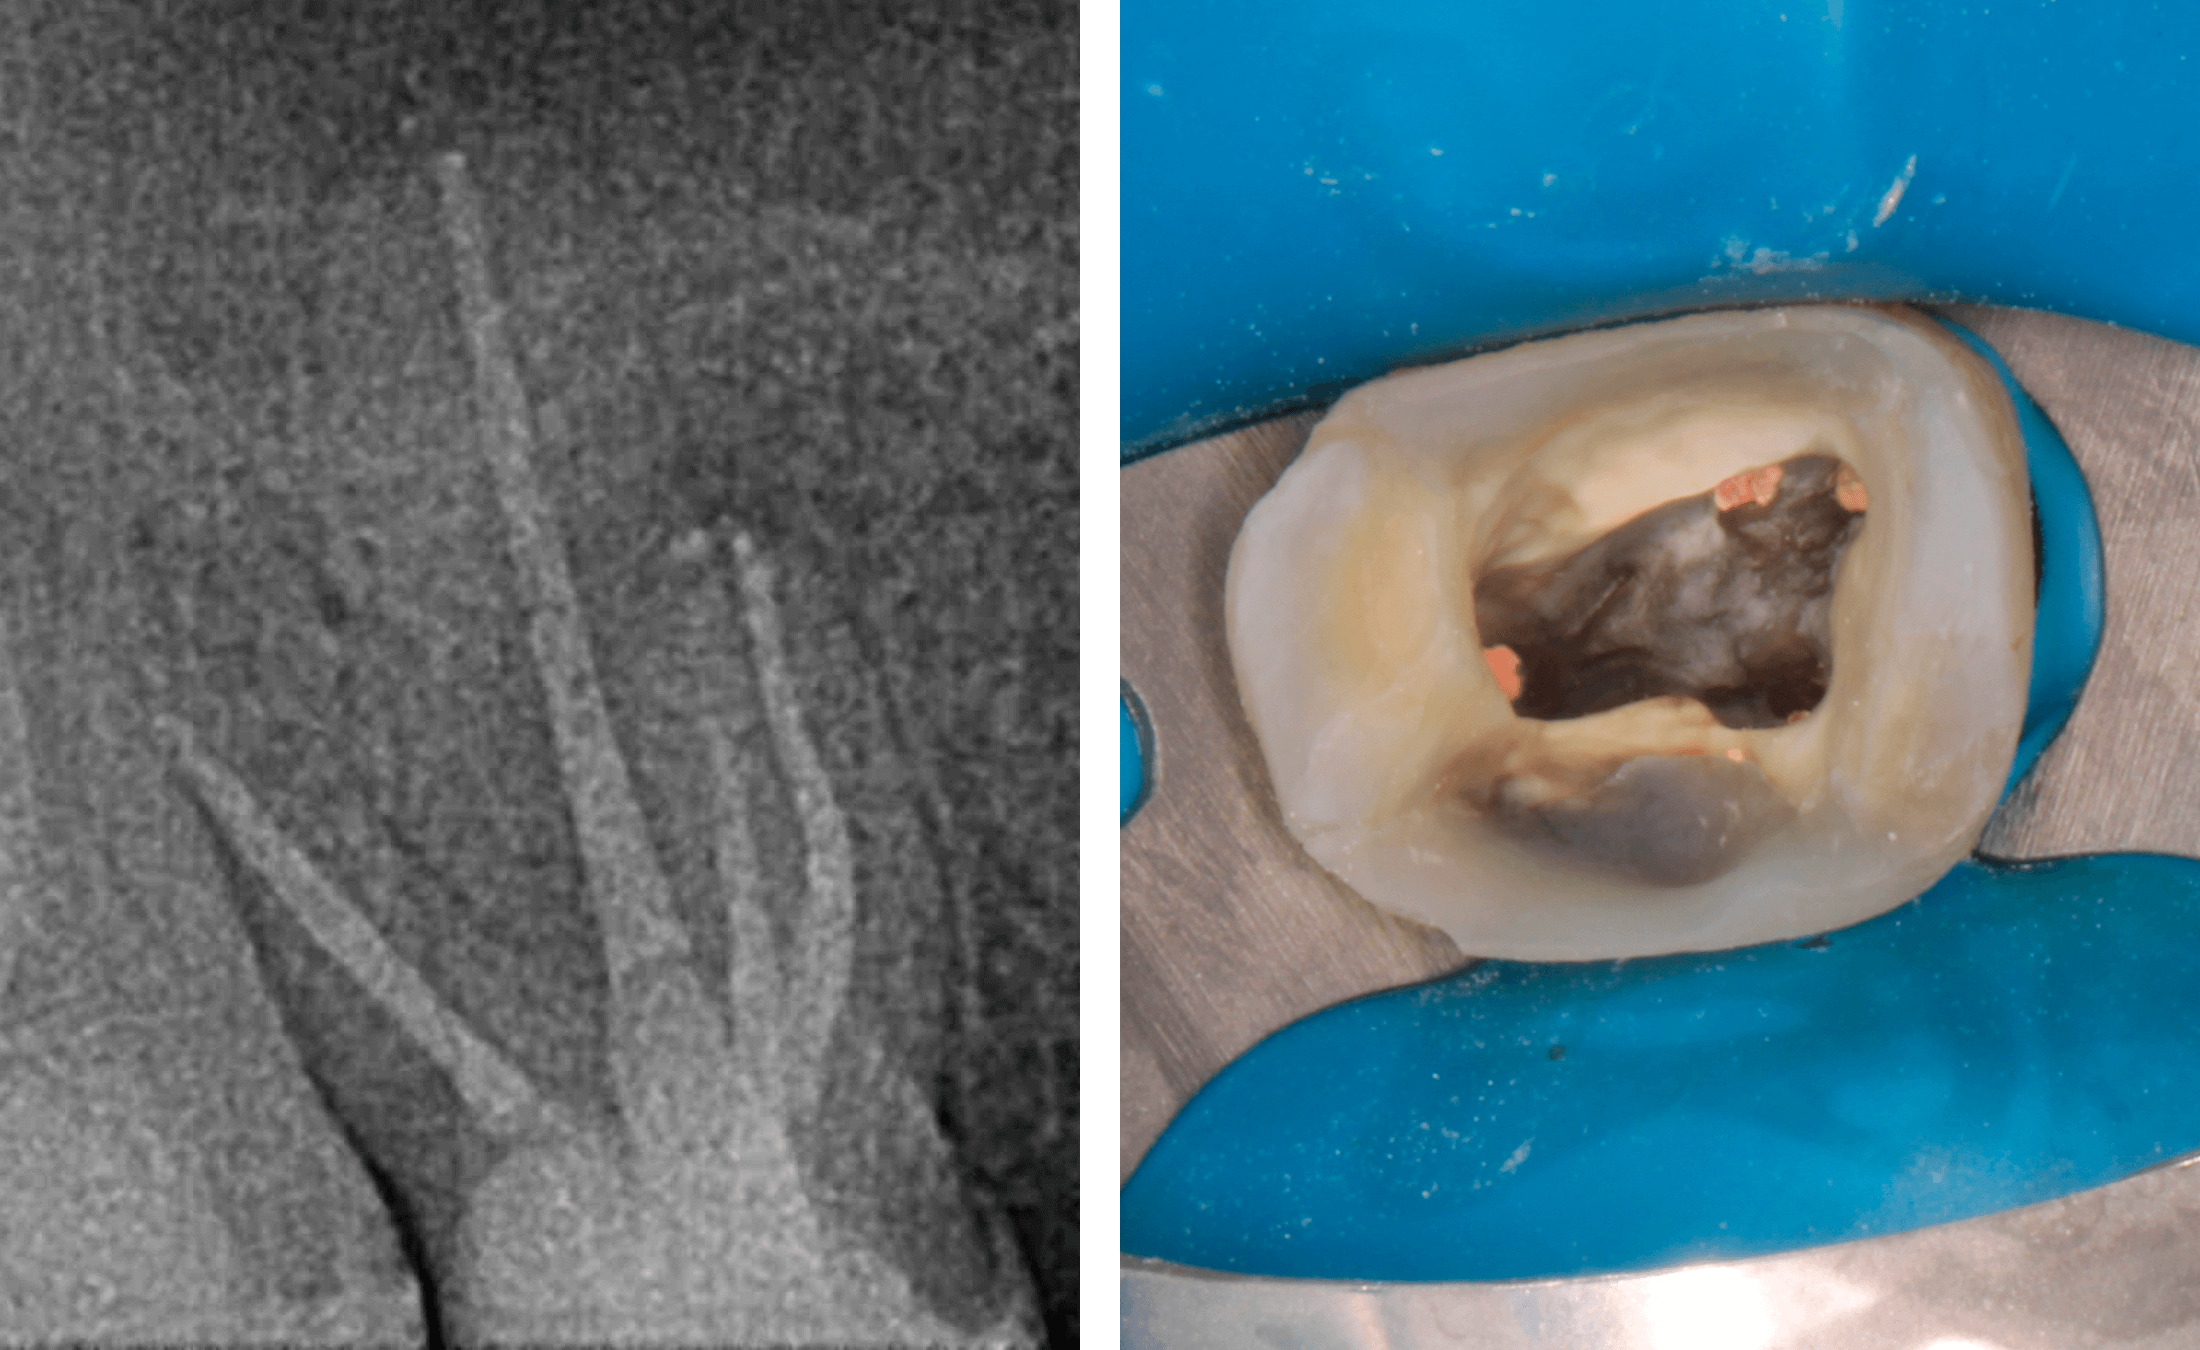

1. Исходная ситуация, зуб 16, апикальный периодонтит, обширная зона перирадикулярной деструкции в области передне-щечного корня, свищевой ход. (Фото 1-4)